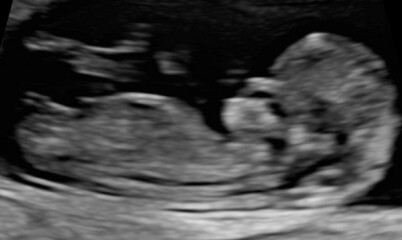

@Janefx40 here's an 11 week scan and 12+6 if you fancy a guess!

@IWillBeWaxingAnOwl your baby is cute! Obviously I really have no idea but my guess is a girl. I'm assuming that white line is the nub but really it could be anything